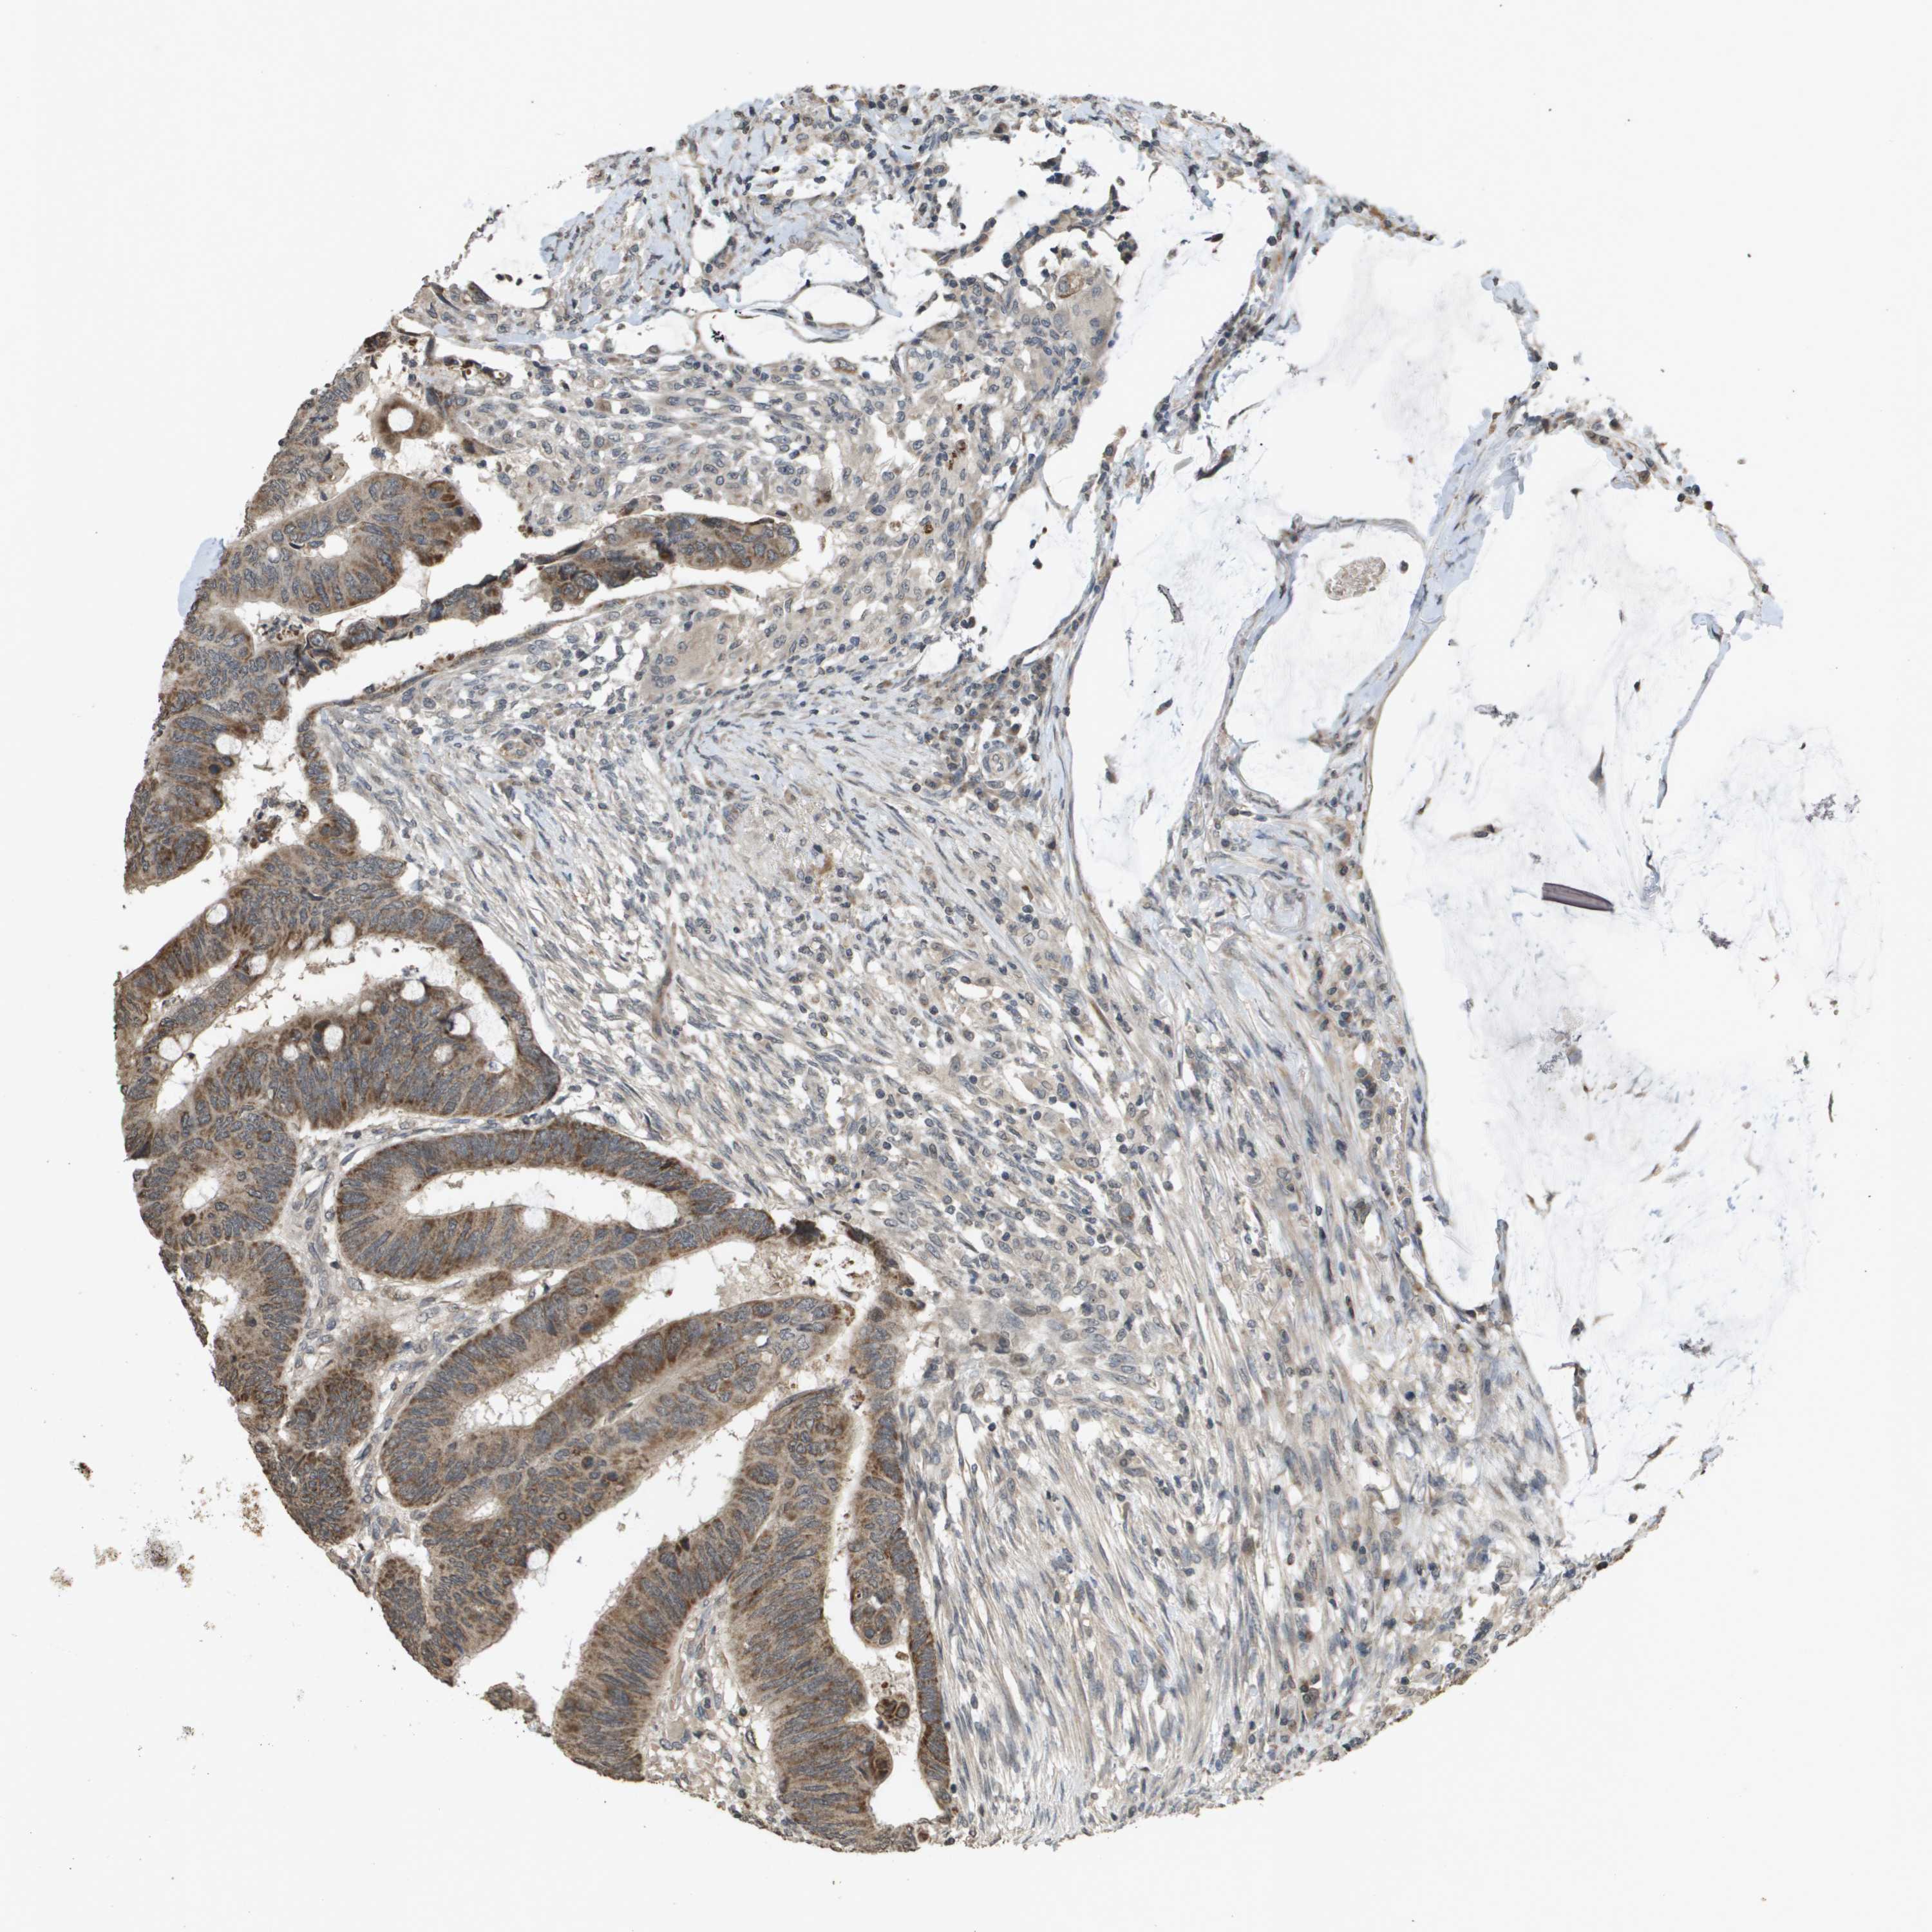

Colorectal cancer

Human cancer